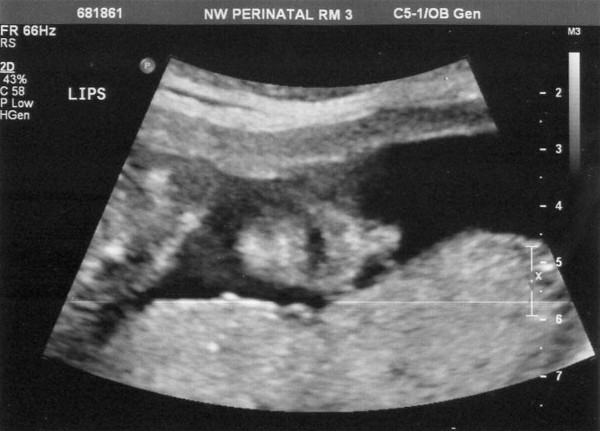

In this first one, it looks like he's blowing a bubble, but since there isn't air in there, we're pretty sure that's not actually what he's doing.

Here is one of his lower face (sideways). The mouth is open and the nostrils of his nose are clearly visible. How fun is that?